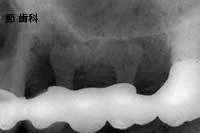

④ この症例は前歯用のブレード型チタンコートPOIインプラント を右上1本目の前歯部に埋入し、隣在する歯とブリッジ状に連結する事で欠損補綴を行ったものです。当時のブレード型POIインプラントは、“ベンダー”にて埋入部分と露出部分の角度設定を施し、無理のない角度で骨内へ埋入出来るようにしていました。